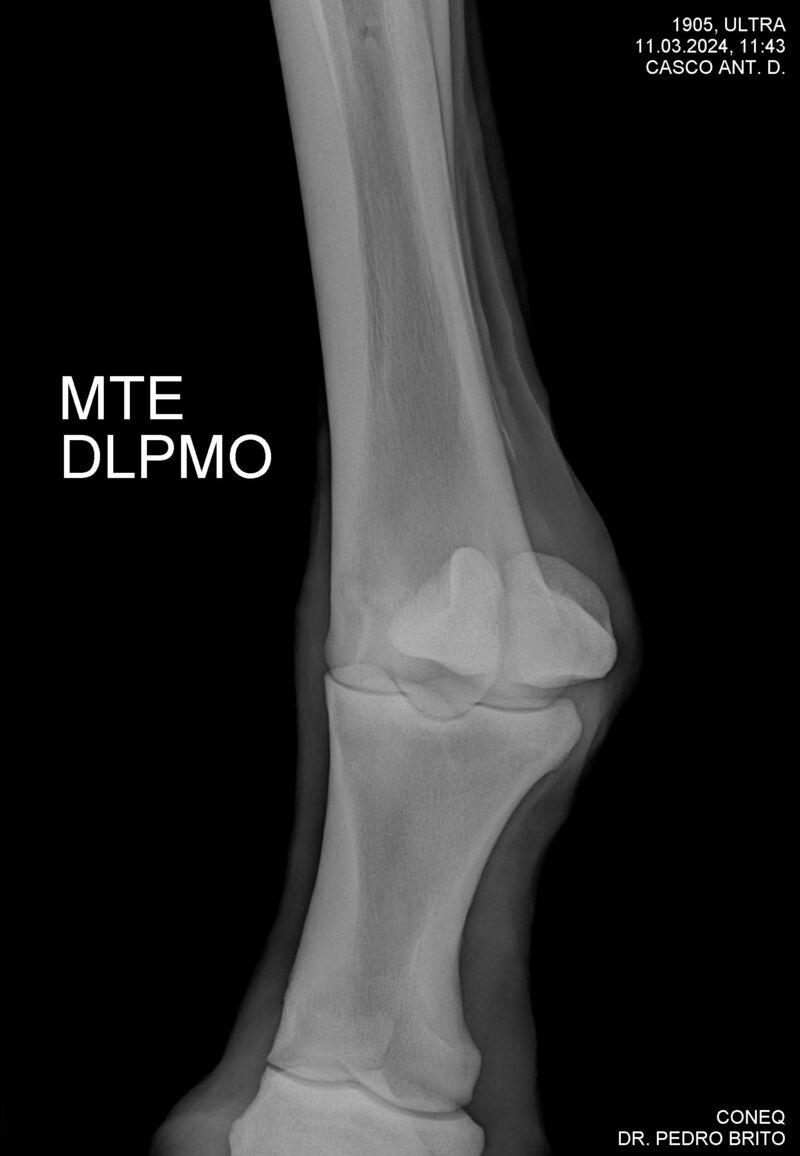

ULTRA DO CACH

Raça: BRASILEIRO DE HIPISMO

Sexo: CASTRADO - CASTRADO

Nascimento: 22/11/2020

Altura Aproximada: 1,67

Pel.: CASTANHO

Registro: 25966-BH

Vend.: HARAS CACHOEIRINHA

Local : PIRASSUNUNGA/SP